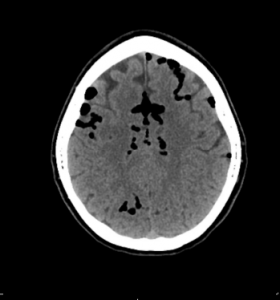

Figures 1 (ABOVE) and 2 (BELOW): CT scan with large-volume atraumatic pneumocephalus.